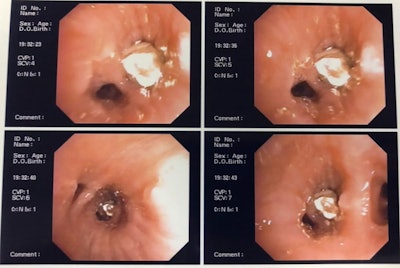

Clinicians then assessed the patient's bronchus using an orotracheal intubation cannula along with a flexible bronchoscope and basket clamp. They chose this method because it has a lower risk of morbidity and mortality, the authors noted.

The scope passed freely through the patient's trachea without alteration of its caliber and without causing mucosal lesions. Using the scope, the team visualized the dental crown, which was obliterating the man's lower lobe bronchus in his right lung.

Clinicians used the basket clamp to grab the upper premolar dental prosthetic crown and then used the cannula to remove it. The procedure was completed without complications, and the patient was reintubated. Approximately one hour passed from the time the clinicians identified the tooth until its removal.

Image of aspirated dental crown captured using a flexible bronchoscope and clamp.Managing a difficult case